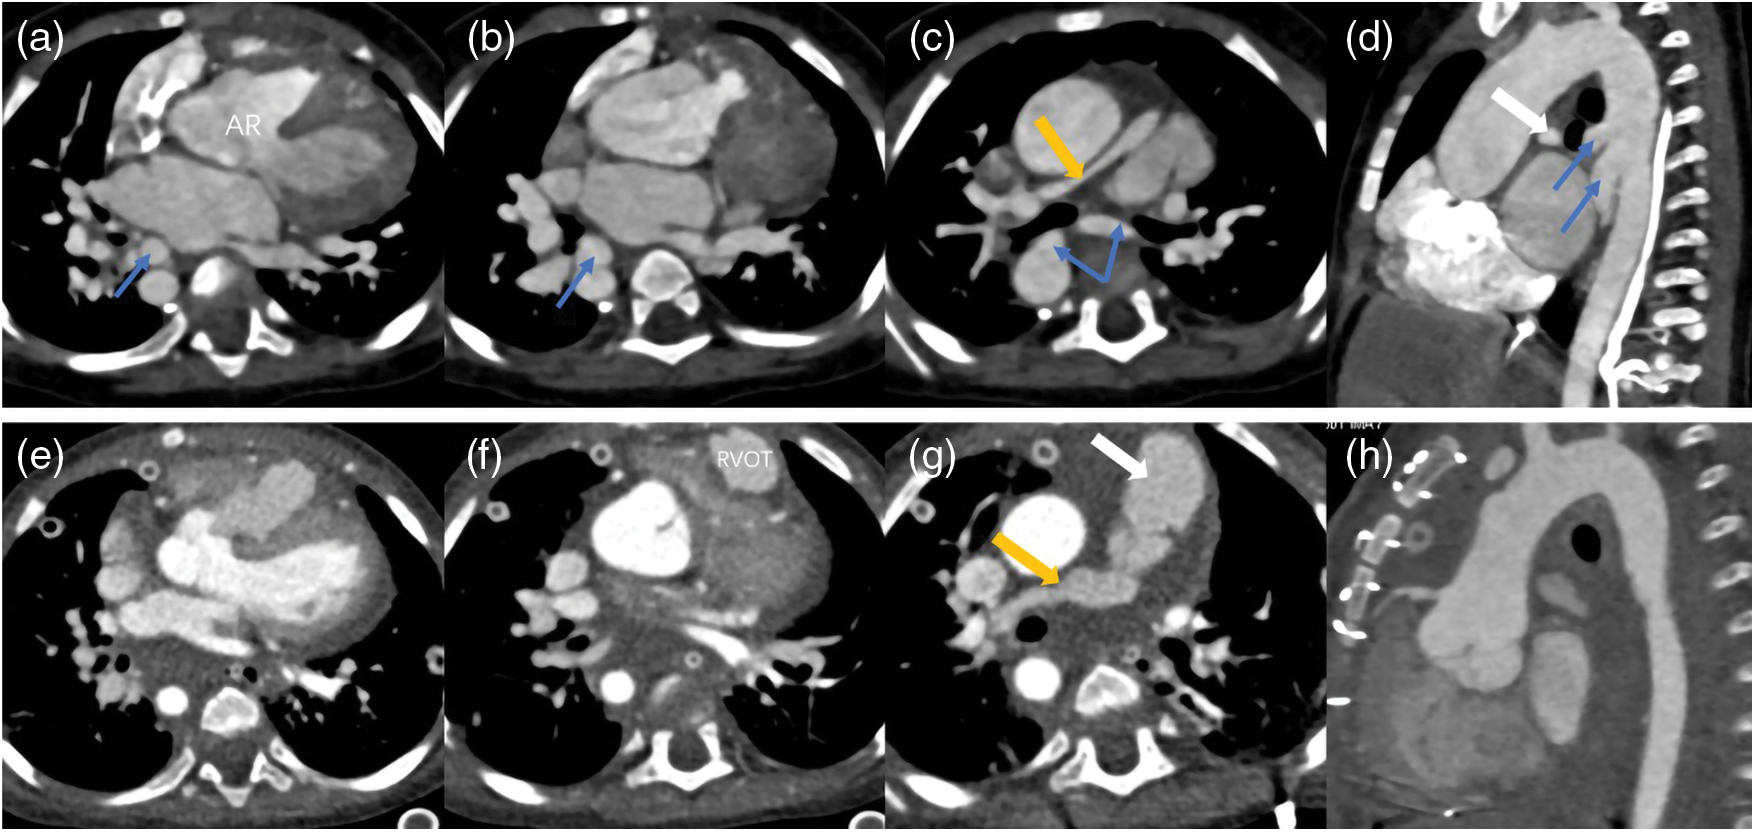

Figure 5: Two sets images of a PA patient who underwent surgery. The images of (a–d) were pre-operation and (e–h) were post-operation. The surgery reconstructed the right ventricular outflow tract (RVOT) and pulmonary trunk (white arrow), repaired the aortic riding (AR), disconnected the MAPCAs (blue arrows) and expanded the right pulmonary artery (yellow arrow) and left pulmonary artery (not shown) by using the disconnected MAPCAs. This patient was accompanied with right aortic arch